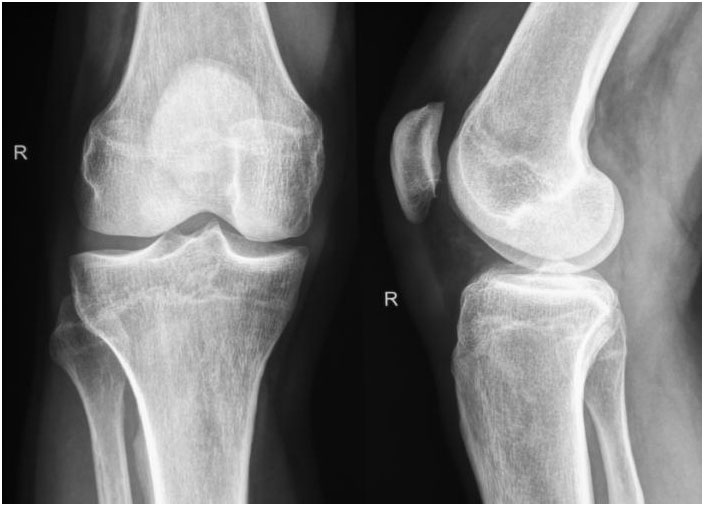

- - Intraarticular fracture– where the break extends into the surface of a joint

Doctors will often order an X-ray. In some cases, an MRI or CT scan may also be ordered.

Physical therapy – after the bone has healed, it may be necessary to restore muscle strength as well as mobility to the affected area. If the fracture occurred near or through a joint, there is a risk of permanent stiffness or arthritis – the individual may not be able to bend that joint as well as before.